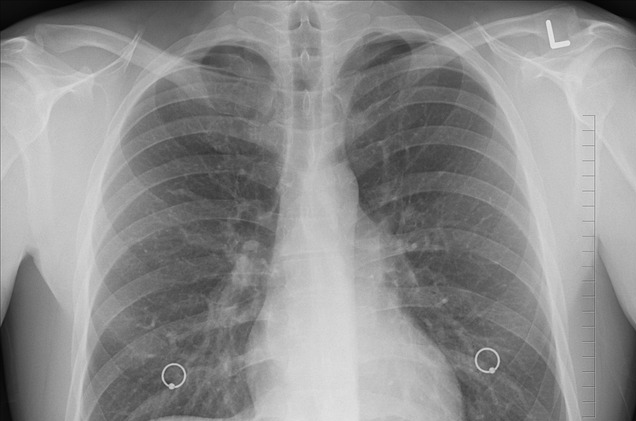

청진 시 수포음이 들릴 수 있습니다. 따라서 환자의 증상과 위험요인들을 종합적으로 판단하여 흡인성 폐렴이 의심되면 흉부 X-ray 검사를 합니다. 검사에서 음영이 보이면 폐렴으로 진단할 수 있습니다. 또한 혈액검사를 통해 전신 염증성 수치들의 증가를 확인하게 되며, 폐렴의 원인균 파악을 위해서 객담에서 객담배양검사를 시행하게 됩니다. 추가적으로 흉부 전산화 단층촬영(CT)을 하여 진단을 확인을 하기도 합니다.